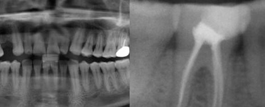

主诉: 右上第一磨牙缺失2年要求种植修复 现病史: 顾客诉右上第一磨牙缺失,给生活带来不便,今来诊 医生诊断: 顾客右上第一磨牙缺...

爱齿尔主任根管治疗重度龋齿案例,右侧后牙疼痛一周,做根管治疗后疼痛消失,且患牙保留……...

所属类别:根尖周囊肿 主治医生:杨金桥主任 顾客22岁,因牙龈肿痛流脓来我院寻求解决方法。 案例回顾 顾客是一位22岁的女性,3年前右...